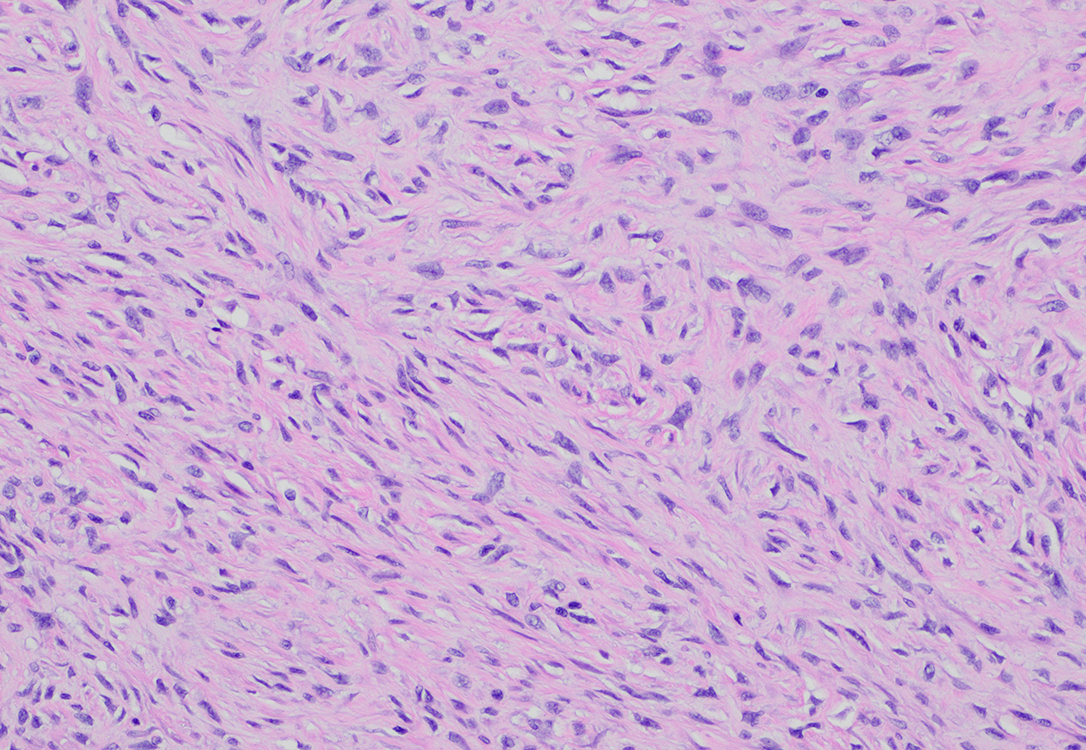

Figure 4_10X